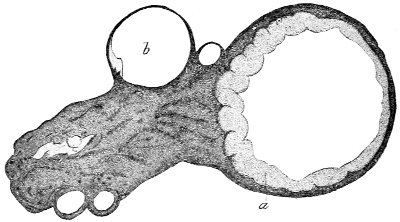

Cysts of the gland may be unilocular if formed at the expense of a single lobule of the gland, or multilocular if several lobules enter into their formation. These cysts may attain the size of the fetal head (Fig. 18).

These cysts contain clear yellow or chocolate-colored 42 fluid. The diagnosis of cyst of the vulvo-vaginal gland is usually not difficult. If we are in doubt in regard to the fluid character of the tumor, this may be determined with the exploring-needle.

Vaginal cysts are usually single. They vary in size from that of a pea to that of a fetal head. The vaginal mucous membrane covers the free surface of the cyst, and may either be movable over it or may be much attenuated and closely incorporated with the cyst-wall. Vaginal cysts may be sessile or more or less pedunculated. The internal surface of the cyst is usually covered with 52 cylindrical epithelium, which is sometimes ciliated. The contents vary in consistency and color. They are often viscid, transparent, and of a pale yellow tint. They may contain pus or altered blood.